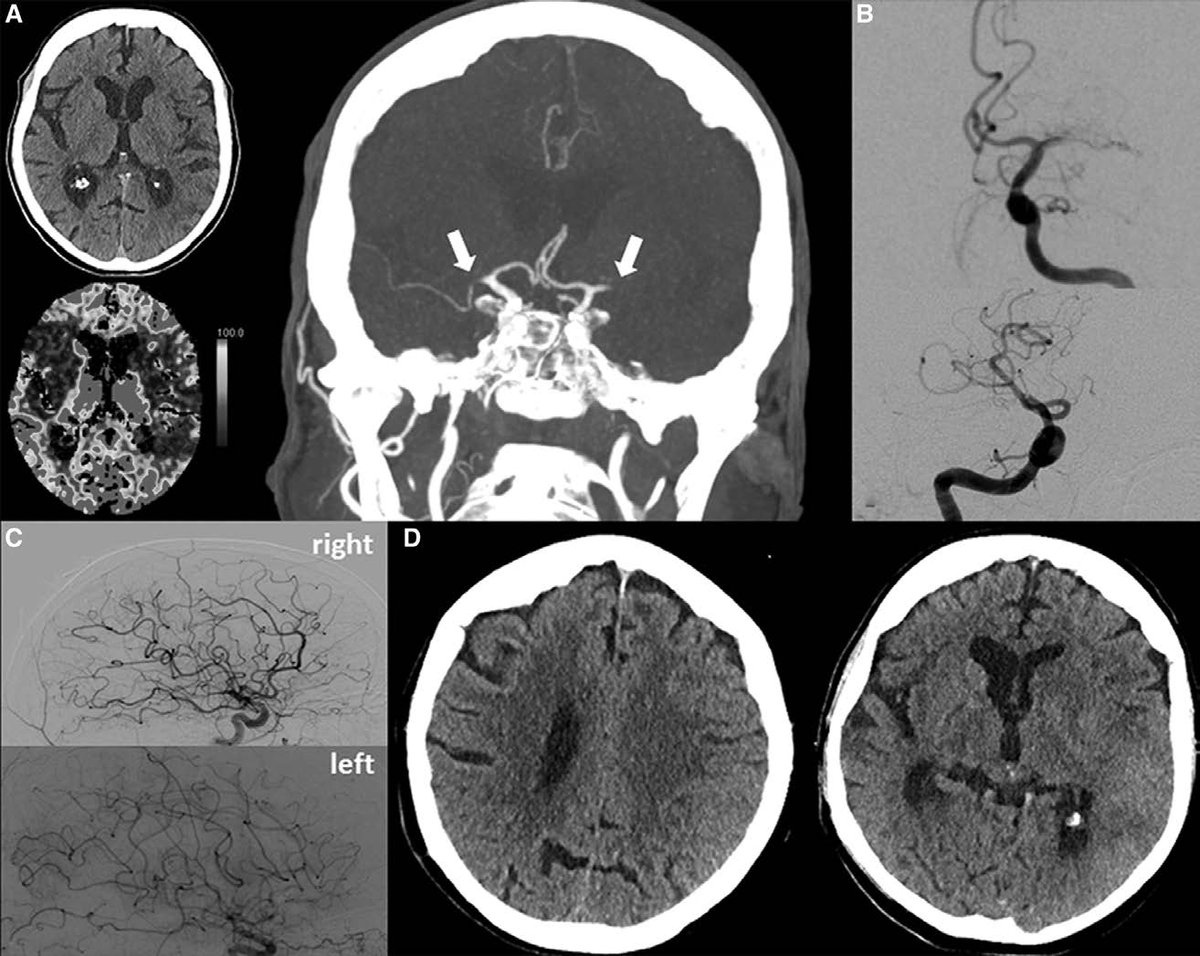

Evolution of thrombectomy devices, developed for treatment of AIS due to arterial LVO improved the safety profile for use in cerebral venous thrombosis. Prospective studies are mandatory! ncbi.nlm.nih.gov/m/pubmed/30980… #Stroke #NeuroRad #neurointervention

Styczen et al: Repeated mechanical thrombectomy in short-term large vessel occlusion recurrence: multicenter study and systematic review of the literature. ow.ly/34xj50zCYGl

Primary Multivessel Occlusions Treated With Mechanical Thrombectomy: A Multicenter Analysis and Systemic Literature Review #stroke ow.ly/KrbK50Aydib